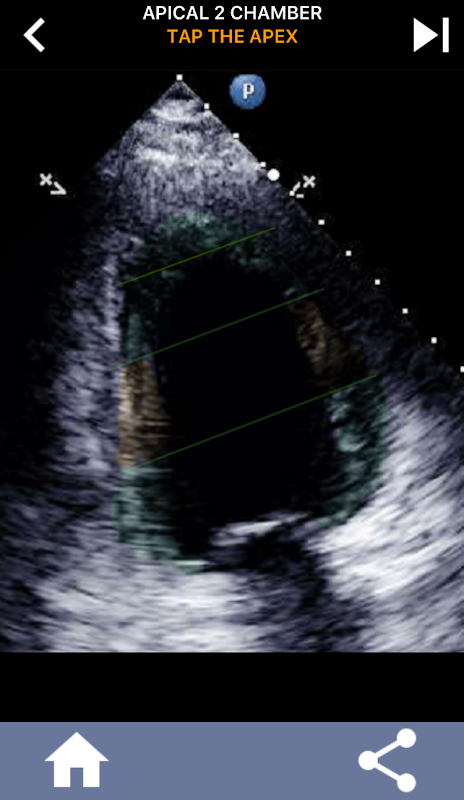

Enfoque visual basado en cuestionarios para aprender los segmentos cardíacos de la AHA: ecocardiografía

Comprender los segmentos cardíacos de la AHA (Asociación Estadounidense del Corazón) es de suma importancia para que un ecografista cardíaco se comunique de manera efectiva con el cardiólogo que escribe el informe. Al conocer las regiones anatómicas específicas y sus segmentos correspondientes, el ecografista puede describir y comunicar con precisión cualquier anomalía o hallazgo, asegurando una comunicación clara y concisa entre ambos profesionales.

Esta comprensión se vuelve particularmente crucial cuando el cardiólogo busca determinar la ubicación precisa de un problema o cuando el médico de guardia identifica un problema dentro de una región específica, lo que hace que el ecografista muestre con precisión el segmento correspondiente, como la pared inferior media. Por lo tanto, poseer una comprensión integral de los segmentos cardíacos de la AHA es un conjunto de habilidades esencial.

Esta aplicación pondrá a prueba su conocimiento utilizando imágenes de eco reales, que a menudo encuentro que es el mejor método de enseñanza.